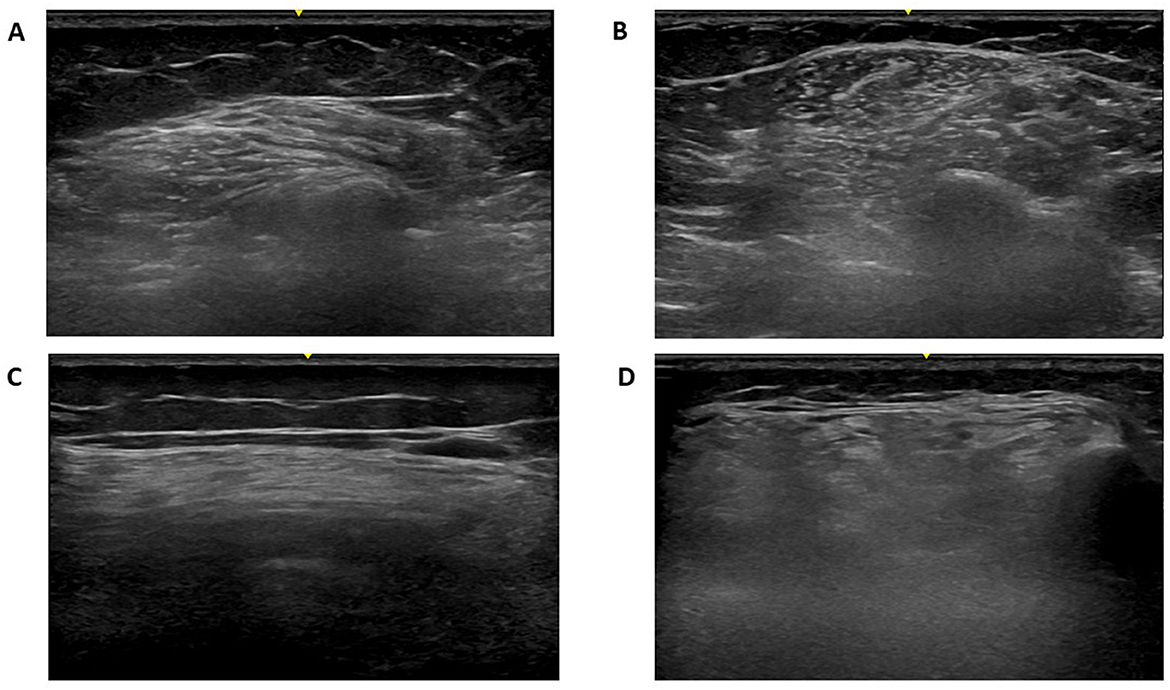

In all patients, muscle ultrasound revealed increased echogenicity suggestive of myopathic involvement, with varying degrees of severity (see Table 3, Figure 3). The vastus lateralis and tibialis anterior muscles most frequently showed higher Heckmatt scores (grades 3–4), consistent with more advanced structural changes in these regions. Patient 5 (see Figure 3). demonstrated the most severe and generalized muscle involvement (grade 4 in three muscles), while patient 1 had milder findings (mostly grade 2). The deltoid and biceps muscles generally showed milder involvement (grades 2–3). Ultrasound evaluation revealed consistent involvement of the tibialis anterior muscle across the cohort. In most patients, the tibialis anterior muscle displayed a degree of structural alteration comparable to the vastus lateralis, and in two cases (patients 1 and 4) the distal muscle was even more severely affected than proximal thigh muscles.

Figure 3

Muscle ultrasound of patient 5 with GFPT1-related congenital myasthenic syndrome demonstrating severe myopathic changes. Muscle ultrasound images from Patient 5 with GFPT1-related congenital myasthenic syndrome, demonstrating advanced myopathic changes graded by the modified Heckmatt scale. (A) Right deltoid (Grade 3) (B) Right biceps brachii (Grade 3); (C) Right vastus lateralis (Grade 4) (D) Right tibialis anterior (Grade 4).

Mean Heckmatt scores ranged from 2.2 to 3.6, indicating varying degrees of muscle echogenicity and structural damage (see Table 3). A strong positive correlation was found between MGFA score and mean Heckmatt echogenicity score (Spearman ρ = 0.918, p = 0.028) (Table 4), suggesting that clinical severity of weakness was aligned with increased structural muscle abnormalities on ultrasound. Specifically, the patient classified as MGFA IVa (Patient 5), who exhibited the most severe phenotype, including early loss of ambulation, also demonstrated the highest mean echogenicity score (Figure 3). Muscle-specific analyses showed no significant correlations between RNS decrements and ultrasound echogenicity: deltoid 39.0–45.7% (mean 43.6%, HS 2–3; p = 1.00) and tibialis anterior 21.7–61.7% (mean 36.5%, HS 3–4; p = 0.23).